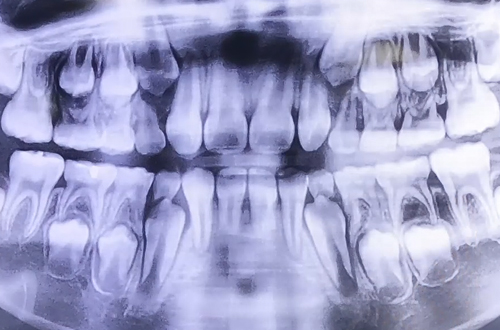

어릴 때 가지고 태어나는 유치가 하나씩 맹출되고 잇몸 속에는 영구치가 묻혀있어, 유치와 영구치가 함께 존재하는 시기를 혼합치열기라고 합니다.

유치는 어떤 과정을 거쳐 빠지게 되는 것인지 그 과정을 포함하여 혼합치열기의 특징은 무엇이 있는지, 어떤 것을 조심해야 하는지 등의 내용을 본원에서 진료 받은 어린이 환자의 엑스레이를 보며 설명해 드립니다!